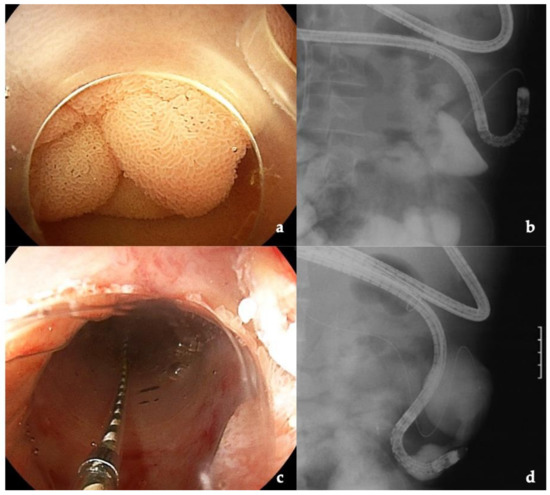

3.4. Intussusception Antireflux Valve